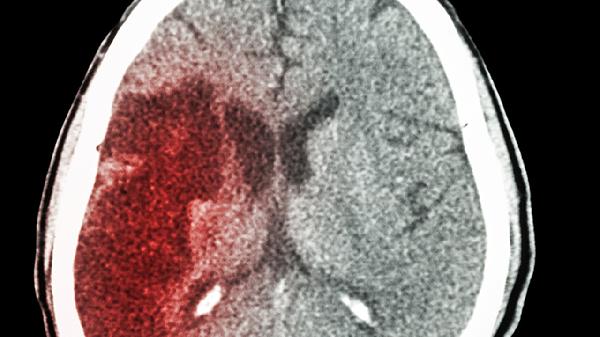

定期复查包括头颅CT检查和神经系统评估。术后1周需复查CT观察血肿吸收情况,之后每3个月评估恢复进度。出现头痛加剧或肢体无力等异常症状时应立即就诊。饮食方面选择低盐低脂高蛋白食物,如清蒸鱼肉豆腐等,避免辛辣刺激性食物。保证每日饮水量但需控制夜间摄入以防起夜跌倒。睡眠时抬高床头30度有助于减少颅内静脉回流压力。保持环境安静舒适,避免强光噪音刺激。心理支持同样重要,家属应耐心倾听并鼓励患者表达情绪。